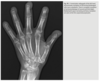

No history - hand pain

Anteroposterior and oblique views of the right hand (Figs. 2.27.1 and 2.27.2) show multiple metacarpal and phalangeal lesions with chondroid matrix, representing enchondromas and numer- ous hand and finger soft-tissue masses containing phleboliths. Maffucci syndrome (i.e., multiple en- chondromatosis with soft-tissue hemangiomas) transformation of enchondromas into chon- drosarcoma in patients with Maffucci syndrome.